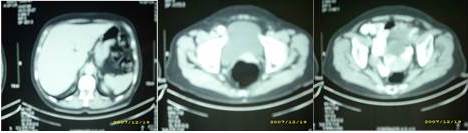

Se solicitan estudios de extensión: tomografía axial computarizada de abdomen y pelvis 15/07/2008: no demuestra imágenes de tipo MT a nivel hepático. No se demostraron adenopatías. Aparente aumento de volumen del cuello uterino en relación al cuerpo uterino que es relativamente pequeño. No se puede evaluar con definición el recto por encontrarse muy distendido al momento del estudio (Figura 3).